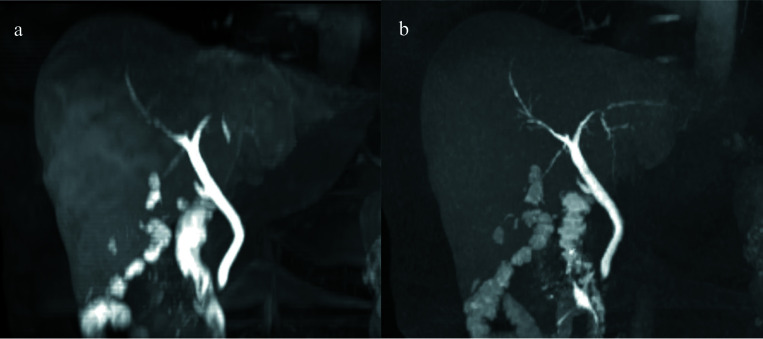

目的:评估在钆醋酸增强肝脏磁共振成像中使用压缩传感(CS)的屏气(BH)高分辨率(HR)T1加权梯度回波肝胆相(HBP)成像与使用平行成像(PI)的标准HBP成像的可行性:研究纳入了122例HBP低密度肝肿瘤患者,他们同时接受了CS的HR HBP成像和PI的标准HBP成像。两位放射科医生评估了肝脏边缘锐利度、肝脏血管清晰度、胆管清晰度、图像噪声和整体图像质量,以及HR和标准HBP成像的病灶清晰度和由HBP图像重建的对比增强(CE)磁共振胆管造影(MRC)图像质量。作为定量分析,还测定了肝脏的信噪比和肝脏与病变信号强度比(LLSIR):结果:使用 CS 进行 HR HBP 成像时,肝脏边缘锐利度、肝血管清晰度、胆管清晰度、整体图像质量以及病变清晰度和 LLSIR 均显著高于标准 HBP 成像(P 均<0.001)。使用 CS 进行 HR HBP 成像重建的 CE-MRC 图像质量也明显高于标准 HBP 成像(P < 0.001)。相反,标准 HBP 成像中肝脏的信噪比明显高于使用 CS 的 HR HBP 成像(P < 0.001):结论:与标准 HBP 成像相比,带 CS 的 BH HR HBP 成像可在不延长采集时间的情况下提高整体图像质量、病灶清晰度和 CE-MRC 可见度。

Results: The liver edge sharpness, hepatic vessel conspicuity, bile duct conspicuity, and overall image quality as well as the lesion conspicuity and the LLSIR on HR HBP imaging with CS were significantly higher than those on standard HBP imaging (all of P < 0.001). The image quality of CE-MRC reconstructed from HR HBP imaging with CS was also significantly higher than that from standard HBP imaging (P < 0.001). Conversely, the SNR of liver in standard HBP was significantly higher than that in HR HBP with CS (P < 0.001).

Conclusion: BH HR HBP imaging with CS provided an improved overall image quality, lesion conspicuity, and CE-MRC visualization when compared with standard HBP imaging without extending the acquisition time.